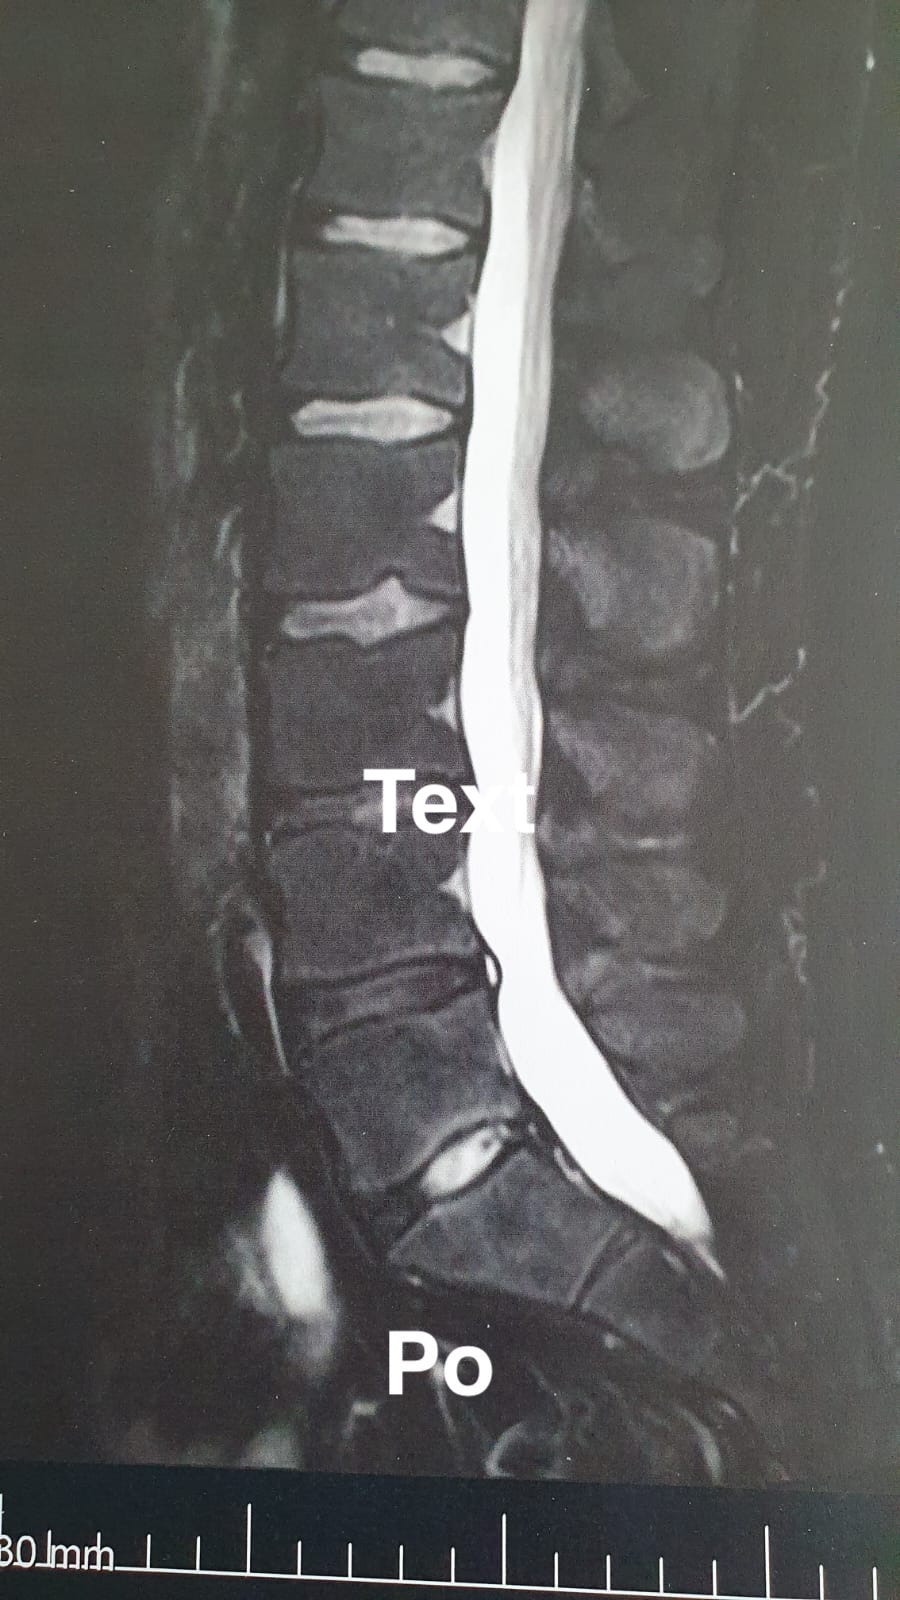

Zdravím, kamarátka, ktorej som odporučil SM system ma poprosila či vám pošlem snímky mojej chrbtice pred začiatkom cvičenia a po 15 mesiacoch. Prvá snímka je z 13.1.2020 a druhá zo 17.4.2021. Pred začiatkom cvičenia som mal problémy už aj s chôdzou, bolesť nekontrolovatelne vystrelovala. Som športovec ale v tomto období 15-tich mesiacov som cvičil len SM system a to asi v priemere 5 krát denne po 15 min. Po 15 mesiacoch som začínal postupne opäť športovať. Dnes športujem naplno a vždy po tréningu si dám 10 min. SM system. Už som vám na kurz poslal plno ľudí a stále posielam. S pozdravom Svatopluk

19.5.22 Ráno mi zazvonil budik do práce a uz som sa nepostavila,necítila som si pravú nohu,3 prsty od malíčka. Po príjme na urgente,ma nabalili infúziami na 2 týždne 2x denne. Bez zlepšenia,následne PRT obstrek pod CT, a po 1.MRi,zákaz chôdze a čakanie na termín operácie. Následne pre návrat citlivosti do prstov zrušenie operácie a začiatok rehabilitácie na poliklinike. Od konca augusta až to teraz dennodenné cvičenie SM. Stav sa postupne zlepšuje, vačšina dní je bez akéhokoľvek obmedzenia.

Väčšina klientov, ktorý pocítia úľavu od problémov s ktorými ku mne prídu nemajú čas a chuť si vybavovať sprievodky na MR-ka, takže bohužiaľ zatiaľ viac výsledkov nemám, ale budem sa snažiť pridávať ďalšie.